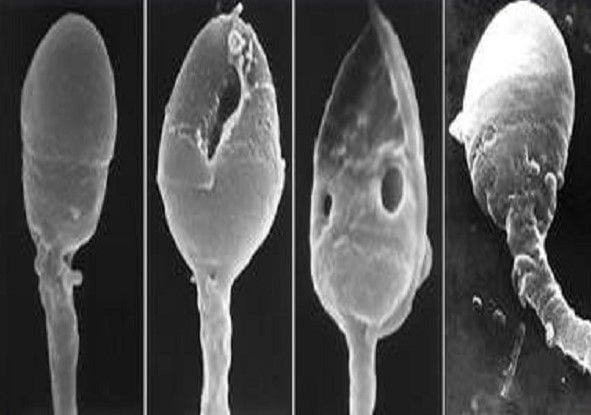

Tuttavia, le nuove scoperte scientifiche, hanno mostrato l’esistenza di determinate caratteristiche morfologiche nello spermatozoo, come ad esempio alcune «bollicine» chiamate vacuoli, la cui presenza indica l’esistenza di una patologia nel suo DNA. Questi vacuoli, essendo molto piccoli di dimensioni, non sono visibili con il metodo di selezione utilizzato fino ad oggi e quindi si è sviluppata la tecnologia IMSI.

I microscopi IMSI, con l’aiuto di lenti speciali, consentono l’ingrandimento dello spermatozoo fino a 10.000 volte, e quindi offrono la possibilità di vedere all’interno della sua testa, un numero maggiore di caratteristiche in modo da permettere di individuare e di scegliere con accuratezza quelli più sani.